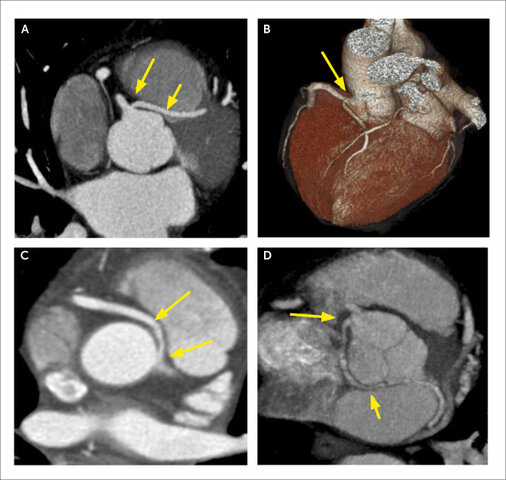

• La TC se utiliza para detectar la enfermedad coronaria.

La TC se utiliza para detectar la enfermedad coronaria.